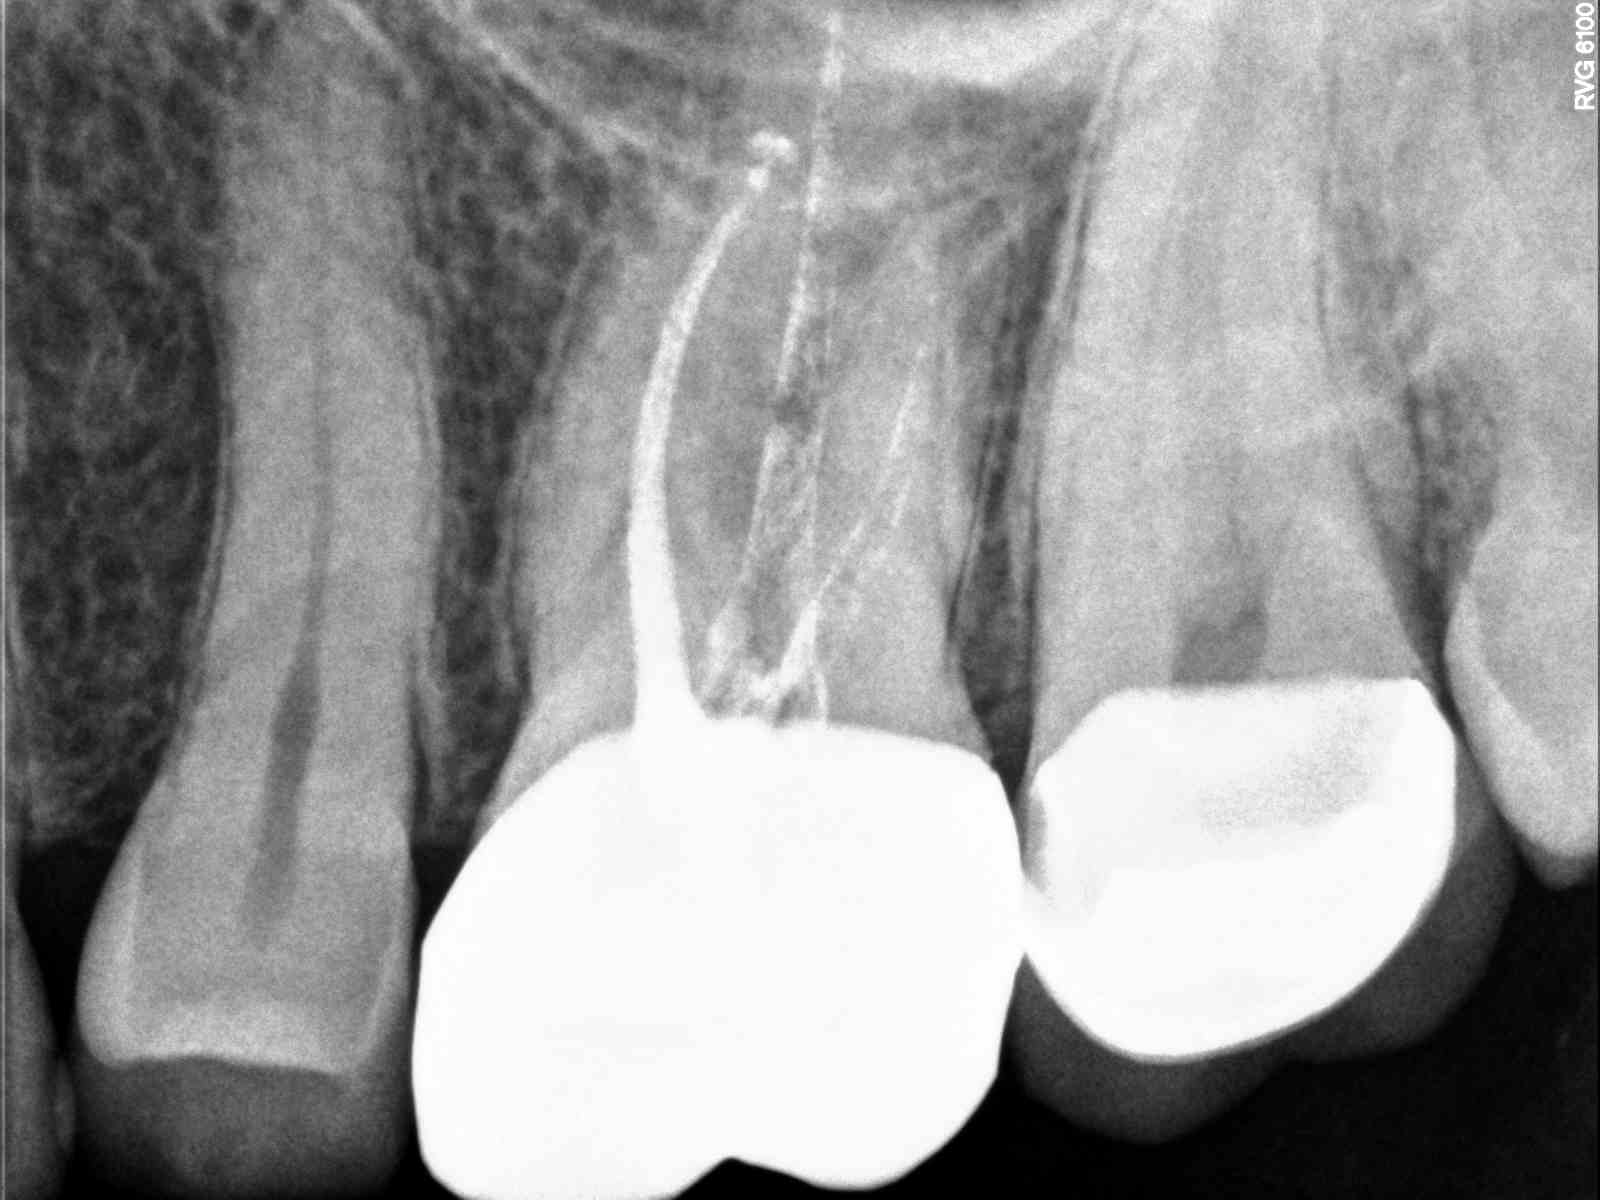

Tooth vital – tooth necrotic

# teeth with MB2 present- able to cleanse and shape the MB2 – MB2 join

MB1 – teeth I consider calcified that no MB2 was found – total # of 1st

molar treated

MB2 distance from MB1 – join MB1

12-11=23

19-16-8-0-23

this was more of a fin than a true second canal-yes